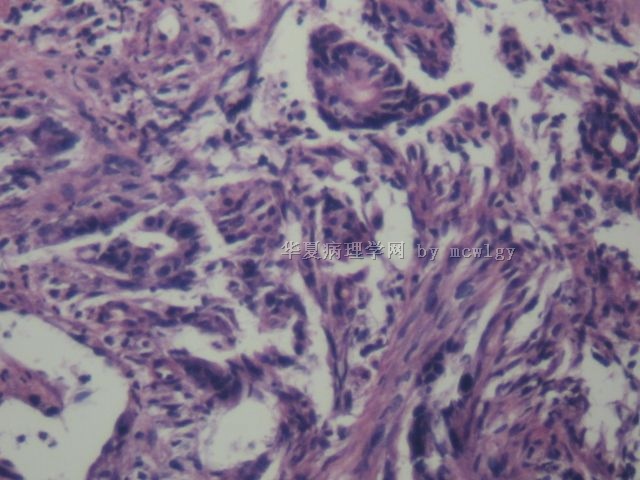

直肠黏膜胃镜取

• 直肠黏膜胃镜取图2

图2

×参考诊断

腺癌

见笑了?片子不好?太简单了直肠腺癌

粘膜肌侵犯,够腺癌了。

腺癌够了。